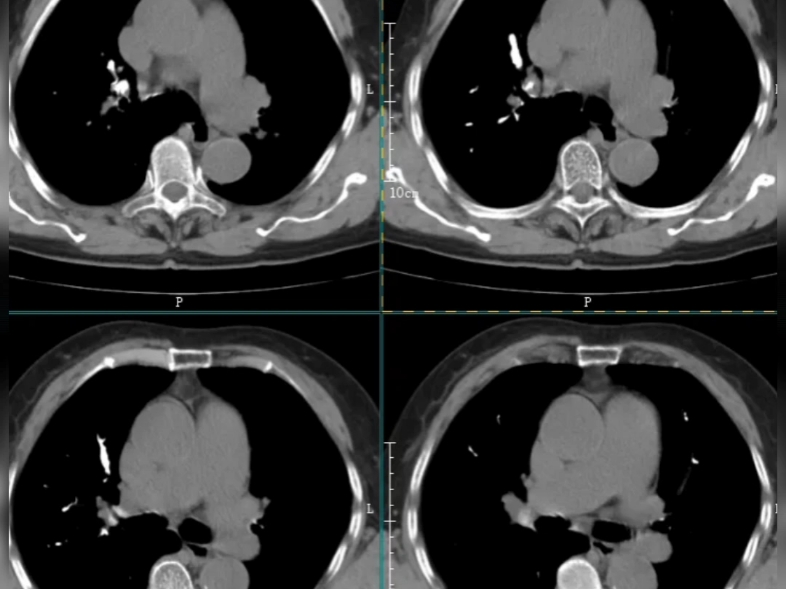

3、肺部钙化灶一般不严重以下是关于肺部钙化灶的详细解答良性状况肺内有钙化灶,临床上通常认为是良性状况或一种相对乐观的情况无影响大多数情况下,肺部钙化灶对身体没有影响,不需要过分担心或进行特殊干预常见原因肺部慢性炎症肺部钙化灶最多见于肺部慢性炎症,如肺结核是目前最常见的原因。

4、钙化病灶区域不广,对肺功能影响小,通常不需要处理,也不会导致特别严重的危害如果大面积的钙化病灶,尤其是大面积的胸膜钙化,也可以导致不同程度的现行通气功能障碍临床大多数情况下的钙化灶都是局灶性,因此不属于严重的疾病,仅仅是以往感染结核杆菌导致肺结核留下来的陈旧病灶。

5、肺部结节钙化灶一般不严重以下是具体分析形成原因肺部结节钙化通常是长时间慢性炎症刺激导致组织增生和钙盐逐渐沉积的结果处理建议肺部结节如果出现钙化,一般不需要过度担心,建议随访观察常见钙化类型错构瘤结节钙化常呈爆米花样肺结核肺部钙化最为常见,但钙化通常不规则没有固定形状。

9、大量的二氧化硅在肺部沉积后,可以形成钙化病灶肺结核经过规范化治疗后,在肺部形成增殖纤维索条钙化等多形性病灶,钙化灶最为常见常见于肺结核本身的病灶吸收,以及肺门淋巴结发生钙化,此时并不严重,没有临床症状,不影响肺功能影像学钙化灶可以长期存在,不容易消失,动态随访就可以所以,肺钙化灶表示陈旧性改变,没有特殊临床意义,不需要特殊治疗,只需要动态随访就可以,本身。

14、可能伴随终生,但通常不会引起任何症状良性病变的预示医生看到钙化灶通常会放心一半,因为钙化灶很多预示是良性病变相反,非钙化的增殖样病变可能会更令人担心,可能是一种活动性炎性或恶性病变特殊情况除非钙化灶特别大特别多,压迫了正常的肺组织,否则散在的钙化灶通常不严重综上所述。

15、肺部点状钙化灶不严重以下是关于肺部点状钙化灶的几点详细说明良性病变肺部点状钙化灶是良性的,只代表曾经的病变,对身体没有实质性影响无需治疗由于钙化灶是陈旧性病变,不会对身体造成危害,因此无需进行特殊治疗常见原因肺部钙化灶最常见的原因是肺结核病造成它是一种肺实质肺细胞。